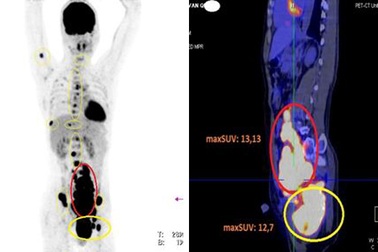

Nam bệnh nhân 35 tuổi ngỡ ngàng phát hiện tế bào ung thư lan khắp ngườiĐi khám vì đau khớp háng, đi lại khó khăn, bệnh nhân được chẩn đoán mắc u lympho ác tính không Hodgkin tế bào B giai đoạn 4, một loại ung thư hệ bạch huyết.